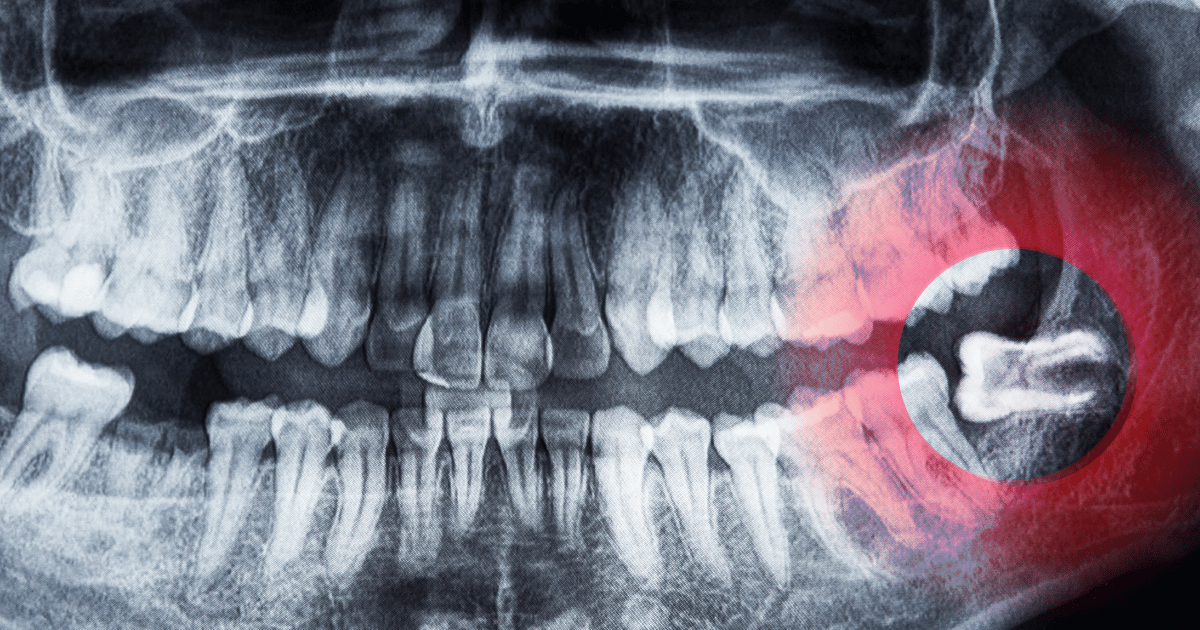

「血餅」が治癒のカギになる理由

抜歯直後、口の中では出血とともに「血餅(けっぺい)」という血の固まりが作られ始めます。血餅は、親知らずの抜歯後に自然にできるもので、治癒に欠かせない存在です。

なぜなら、血餅が傷口をふさぎ、細菌の侵入を防ぐ役目を果たすからです。

例えば、抜歯当日に激しくうがいをすると、この血餅がはがれてしまい、骨がむき出しになります。

そうなると「ドライソケット」になり、激しい痛みや治癒の遅れにつながります。

冷たい風がしみたり、口を開けただけで痛んだりする場合は、血餅がうまくできていない可能性もあります。

抜歯した直後は、水で軽くゆすぐ程度にとどめましょう。血餅を守ることが、回復への第一歩です。